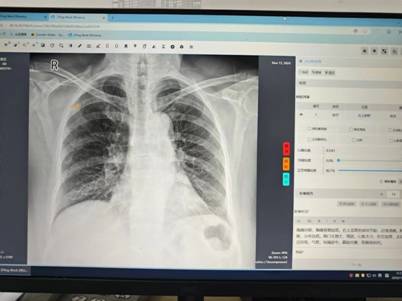

江苏省卫生健康云影像平台作为省级重点惠民医疗信息化工程,构建起全省医学影像数据共享体系,具备影像存储管理、跨区域调阅共享、检查结果互认及重复检查预警等功能,能够对胸部 x 光、ct 等影像进行智能分析。在肺结核早期诊断中,该平台的 ai 智能阅片系统通过抓取胸片关键信息并反馈诊断结果,一旦与原诊断存在差异,医院将立即组织专家复核,必要时安排进一步检查或转诊上级医院,有效减少漏诊误诊,提升基层结核病发现率。

我市积极推动基层医疗卫生机构应用省云影像平台 ai 诊断技术,为结核病防治工作开拓新路径、注入新动能。2024 年,全市已有 5 家基层医疗卫生机构完成省云影像平台 ai 诊断技术部署并投入使用。今年 5 月,又有 14 家基层医疗卫生机构成功纳入省云影像平台 ai 技术系统,目前正有序推进接入工作。下一步,我市将加快申报机构的系统对接与技术落地,充分发挥 ai 技术在肺结核早诊早治中的优势,全力提升早期筛查与临床诊断的精准度和时效性。